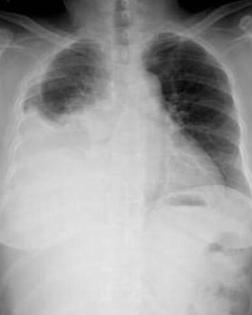

♥胸腔积液

胸腔积液实际上是胸膜腔积液。正常人胸膜腔内有3~15ml液体,在呼吸运动时起润滑作用,但胸膜腔中的积液量并非固定不变。即使是正常人,每24小时亦有500~1000ml的液体形成与吸收。胸膜腔内液体自毛细血管的静脉端再吸收,其余的液体由淋巴系统回收至血液,滤过与吸收处于动态平衡。若由于全身或局部病变破坏了此种动态平衡,致使胸膜腔内液体形成过快或吸收过缓,就会产生胸腔积液(简称胸液)。胸腔积液可分为漏出液、渗出液、脓胸、血胸、乳糜胸,针对不同的症状,应给予相应的治疗。